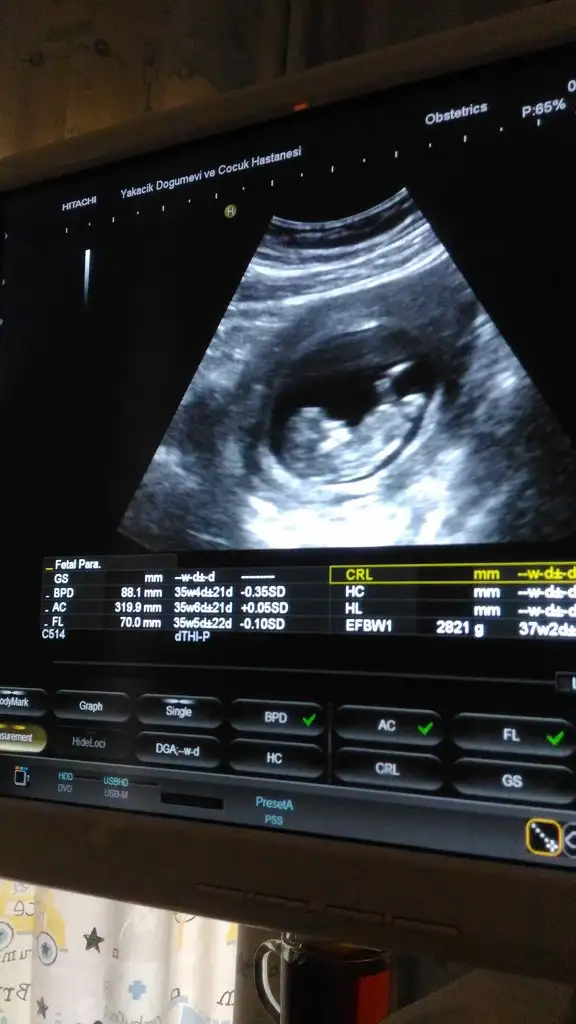

Ben buraya atmamistim nubu. Bilenler yorum yapabilir. İkili testte de risk cikmadi. Birdahaki kontrole 16.haftada falan gitmeyi dusunuyorum o da cinsiyet icin bakalim

Eklentiler

• P_20190704_103309.webp

32,3 KB · Görüntüleme: 83